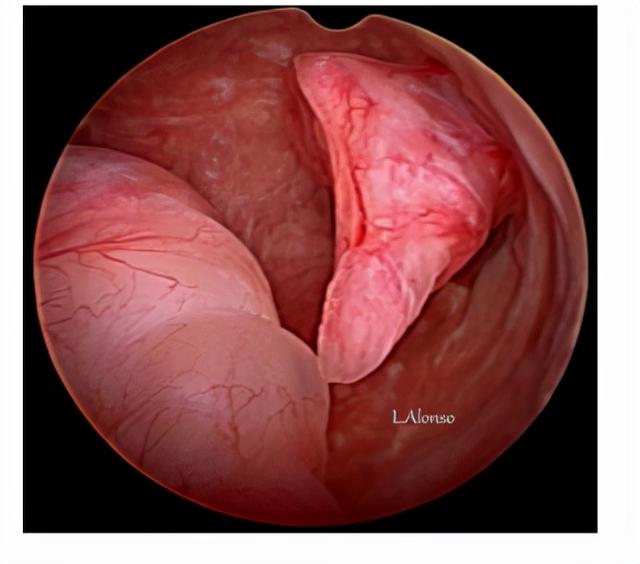

在顺义妇儿医院妇科门诊,经常会有患者问到关于子宫内膜息肉的各式各样的问题。妇二科副主任医师纪翠红指出,子宫内膜息肉是一种常见的妇科疾病,多见于35岁以上女性,随年龄增长发病率也增高。我国女性息肉发病率24-25%,还是非常高的。子宫内膜息肉是子宫局部内膜过度生长造成的,可单个或多个,可小也可大。

3.对于有异常出血症状,或者有息肉的不孕患者考虑手术治疗,不建议盲目刮宫,容易漏诊,复发及息肉破碎,影响病理检查。建议宫腔镜息肉切除术。息肉切除后可以提高怀孕机率。